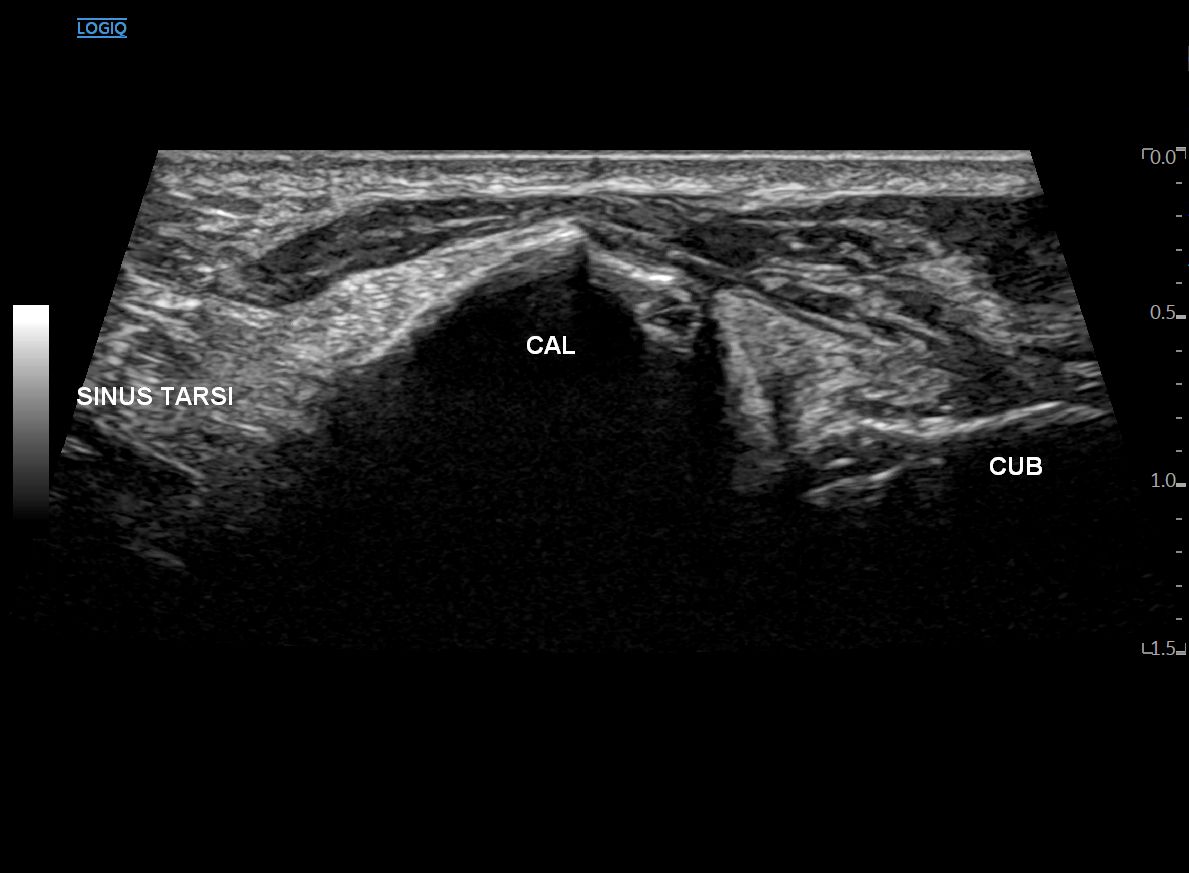

좀 더 안쪽으로 이동하면

종골이 움푹 꺼지면서

족근동(Sinus tarsi)이 보이기 시작합니다.

종입방인대가 끝나면

프로브를 주상골을 향해서 사선으로 돌립니다.